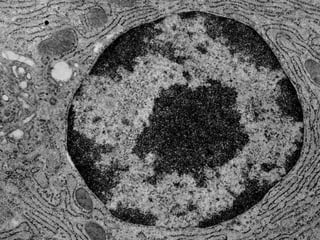

Este documento presenta imágenes microscópicas de diferentes tipos de tejidos y estructuras celulares teñidas con varios métodos histológicos. Incluye fotografías que muestran fibras de colágeno, elásticas y reticulares en diversos órganos, así como membranas basales y células especializadas de órganos como riñones, glándulas mamarias y próstata. El propósito es demostrar la aplicación de técnicas histológicas para visualizar componentes celulares y tej